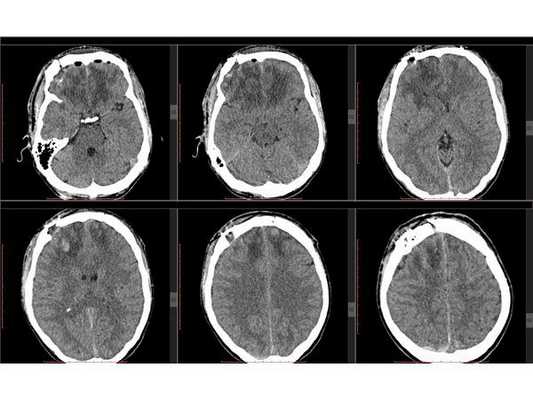

- Субдуральная ( между твёрдой мозговой оболочкой и веществом головного мозга) и эпидуральная ( между внутренней поверхностью костей черепа и твёрдой мозговой оболочкой) гематома в правом полушарии.

- Травматическое субарахноидальное (в полость между паутинной и мягкой оболочками мозга) кровоизлияние.

- Отёк головного мозга.

- Пневмоцефалия (скопление воздуха внутри черепной коробки).

- Умеренное латеральное смещение срединных структур влево до 4 мм.

- Оскольчатый вдавленный перелом правой теменной кости.

- Линейный перелом затылочной кости.

- Перелом клеток решётчатого лабиринта справа с признаками эмфиземы (скопления воздуха) тканей правой орбиты.

- Гемосинус (скопление крови в придаточной пазухе носа) клеток решётчатого лабиринта справа.

На контрольной КТ головного мозга в послеоперационном периоде видна положительная динамика: состояние после краниотомии, репозиции вдавленных фрагментов теменной кости, удаления субдуральной гематомы, регресса дислокации срединных структур стабильное.